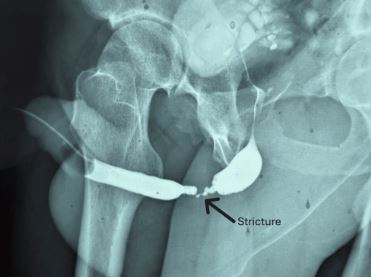

±×·¯³ª ½Ã°£ÀÌ Áö³ª¸é¼ ȯÀÚ¿¡°Ô ¼Òº¯ ÁٱⰡ Á¡Á¡ °¡´Ã¾îÁö´Â ¹è´¢ Àå¾Ö°¡ ³ªÅ¸³ª±â ½ÃÀÛÇß´Ù. »ç°í ¹ß»ý ¼ö³â µÚ ÁøÇàµÈ Á¤¹Ð °Ë»ç¿¡¼ ¿äµµ ³»ºÎ ¾à 4cm ±¸°£ÀÌ µüµüÇÏ°Ô ±»¾î Á¼¾ÆÁø ¡®¿äµµ ÇùÂø¡¯ÀÌ ¹ß°ßµÆ´Ù. ÀÇ·áÁøÀº ȯÀÚÀÇ ÀÔ¾È Á¡¸·À» ¶¼¾î À̽ÄÇÏ´Â ±¸° Á¡¸· ÀÌ½Ä ¿äµµ ¼ºÇü¼úÀ» ÅëÇØ ¼Õ»óµÈ ºÎÀ§¸¦ Àç°ÇÇß´Ù. ¼ö¼ú ÈÄ È¸º¹Àº ¼øÁ¶·Î¿üÀ¸¸ç, 6°³¿ù ÃßÀû °Ë»ç¿¡¼ Á¤»óÀûÀÎ ¹è´¢ È帧ÀÌ È®Àεưí, ÇùÂø Àç¹ßµµ ³ªÅ¸³ªÁö ¾Ê¾Ò´Ù.